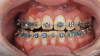

Fig 18. Bite interdigitation to finalize surgical orthodontic correction. After orthodontics, periodontal plastic surgery, bleaching, microabrasion, and restorative dentistry were performed.

Figure 18

Fig 19. Bite interdigitation to finalize surgical orthodontic correction. After orthodontics, periodontal plastic surgery, bleaching, microabrasion, and restorative dentistry were performed.

Figure 19

Fig 20. Bite interdigitation to finalize surgical orthodontic correction. After orthodontics, periodontal plastic surgery, bleaching, microabrasion, and restorative dentistry were performed.

Figure 20